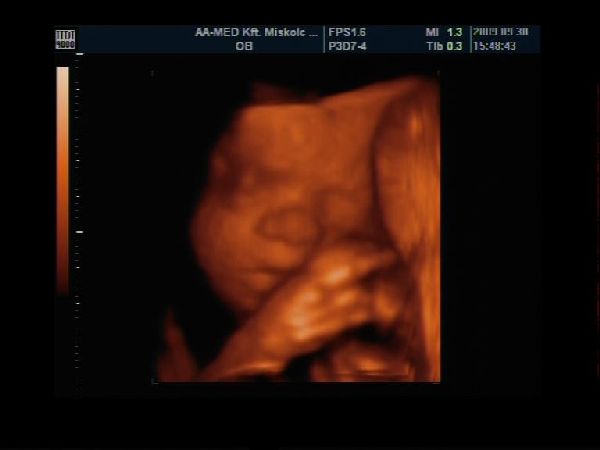

Magzatdiagnosztika Közp.

28. heti Uh Kép